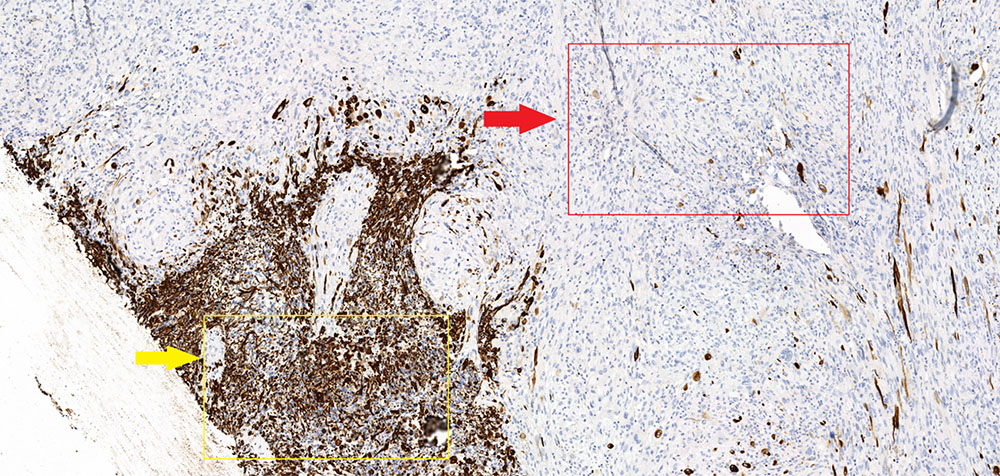

Маркер GFAP (специфичный глиальный фибриллярный кислый белок) – демонстрирует характерную выраженную экспессию в глиальной части опухоли (желтая стрелка) и полное отсутствие экспрессии в саркоматозной (красная стрелка). Кроме того в данном микропрепарате стоит отметить отчетливое преобладание саркоматозной части над глиальной.

N.В.! В зависимости от количества саркоматозной и глиальной ткани отмечаются вариации, при этом если саркоматозная ткань преобладает, то опухоль подобна метастазу (хорошо отграниченная и плотная), в случае превалирования астроцитарного(нейроглиального) компонента опухоль идентична классической глиоблатоме (Louis DN, Ohgaki H).